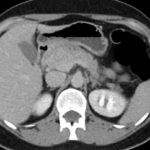

Tomografía de abdomen con cte ev: del 26/10/2023.

Estudio histopatológico reveló neoplásica de estirpe neuroendocrina bien delimitada.

Ahora bien, como se mencionaba al principio, el estudio ecográfico es de muy baja sensibilidad y se identifique o no la lesión por este estudio, nuestro siguiente paso en el algoritmo diagnóstico de esta lesión es la tomografía. Esta es la prueba no invasiva inicial, con una sensibilidad del 63% al 83%, y detecta del 70% al 80% de los tumores. Esta debe realizarse como un estudio trifásico: fase arterial temprana a los 30 segundos, fase venosa a los 70 segundos, fase tardía de 3 a 5 minutos. La característica de estos tumores por tomografía es que se presentan como una masa sólida que tiene un ávido realce en la fase arterial, cuyo realce se mantiene y se observa más tenue en la fase venosa y en los tiempos tardíos la lesión se homogeniza.

Para mi caso, y dando una visión general de los métodos de imagen no invasivos en esta revisión retrospectiva, solo a uno de los pacientes se le detectó la lesión por ecografía, donde se visualizó una lesión nodular hipoecogénica en el cuerpo del páncreas. A los demás pacientes se les detectó la lesión por tomografía en estudio trifásico, donde resaltan las características ya descritas por la literatura de lesiones hipervasculares con intenso realce en fase arterial, localizadas en diferentes partes del páncreas, como cabeza, cuerpo y cola.